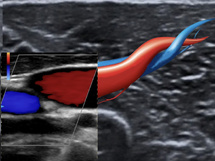

Le Doppler est un outil diagnostique puissant qui permet d’explorer efficacement les flux vasculaires et d’apporter des réponses précises dans de nombreuses situations cliniques. Cette formation complète vous propose de découvrir les bases théoriques et pratiques de son utilisation, spécifiquement adaptées aux besoins de la médecine générale.

- Améliorez vos diagnostics : Identifiez rapidement des pathologies vasculaires comme les sténoses, les thromboses ou les insuffisances veineuses.